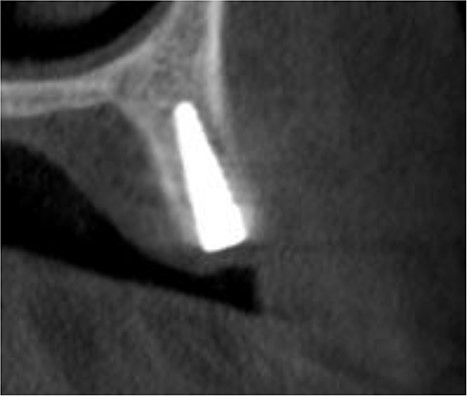

The implant was exposed 6 months postoperatively and the healing caps were placed. CBCT scans were taken to assess gained bone width (Fig. 3). The mean alveolar ridge width before surgery was 4.56 mm. After 6 months, the mean alveolar ridge width was 7.23 mm.

A CBCT scan 6 months after surgery showed formation of new bone buccally, and the entire dental implant being surrounded by bone.